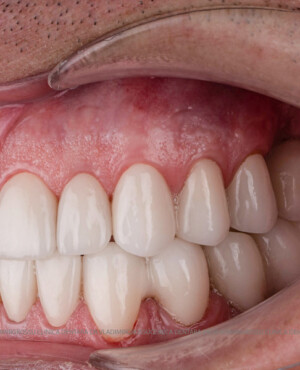

- Estetică superioară – imită perfect dinții naturali

- Funcționalitate completă – mestecare și vorbire fără restricții

- Coroane din zirconiu sau ceramică integrală

- Materiale premium – zirconiu, ceramică E-max, titan pur